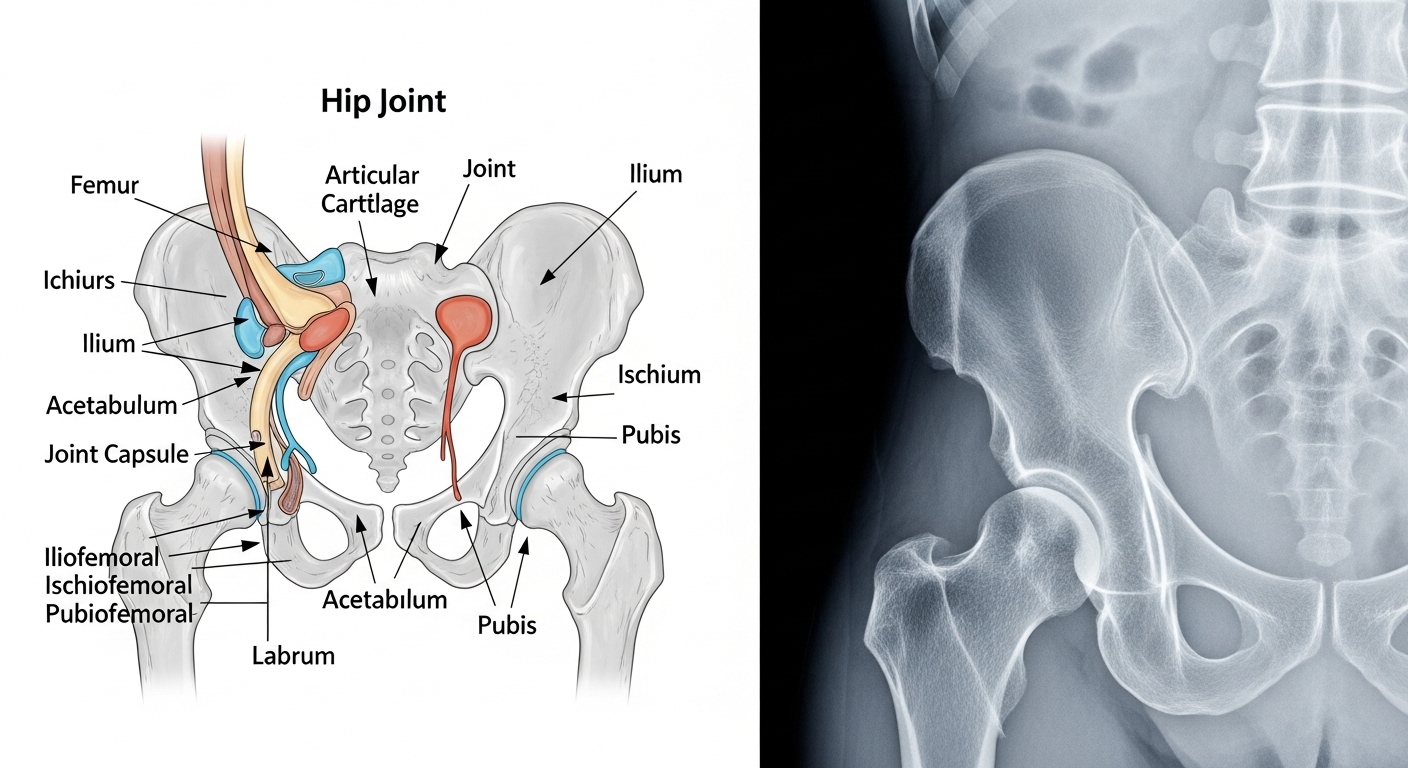

変形性股関節症は、股関節の軟骨がすり減ることで炎症や変形を起こし、痛みや可動域の制限が出る病気です。

- 臼蓋形成不全(股関節の受け皿が浅い先天的な状態)

- 股関節インピンジメントなど構造的異常